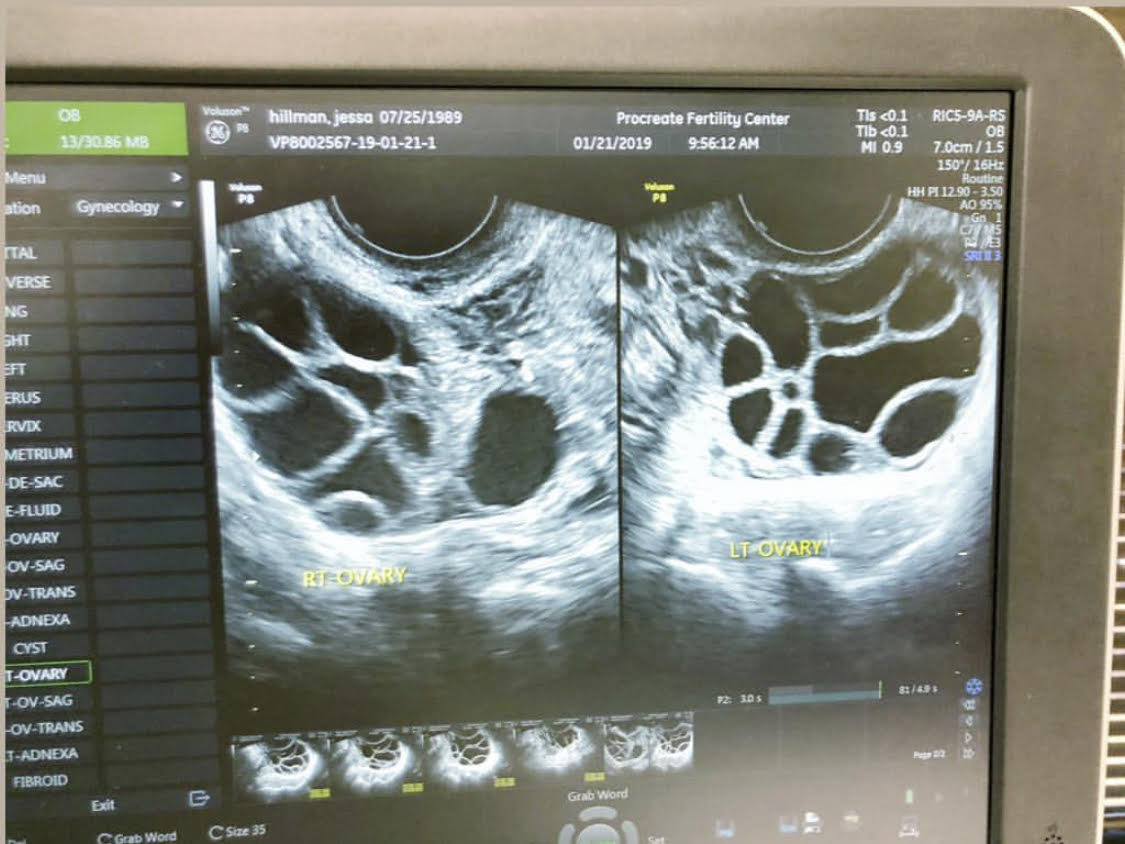

I had regular check ups at our fertility clinic, and they checked me to make sure I wasn’t at risk of experiencing ovarian hyper-stimulation syndrome. I had two internal ultrasounds where the doctor was actually able to look inside my ovaries and count the number of follicles I had, and even measure them to see how mature they were getting. It was amazing! The doctor was very happy with my progress – at the time, we were noticing around 20 follicles, which meant roughly 20 eggs maturing.